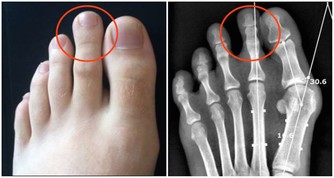

臨床上,經常見到因各種疾病,尤其是癌症,各種器官全切的情況。所以以上分析都是純理論的情況,結合各個器官的功能進行的分析。人體是一個有機的整體,特別是吸收、代謝等維持人體正常生理功能的器官至關重要。有的器官,少之,生命必受影響,甚至短時間內就會死亡。而有的器官則無礙於生命長短。